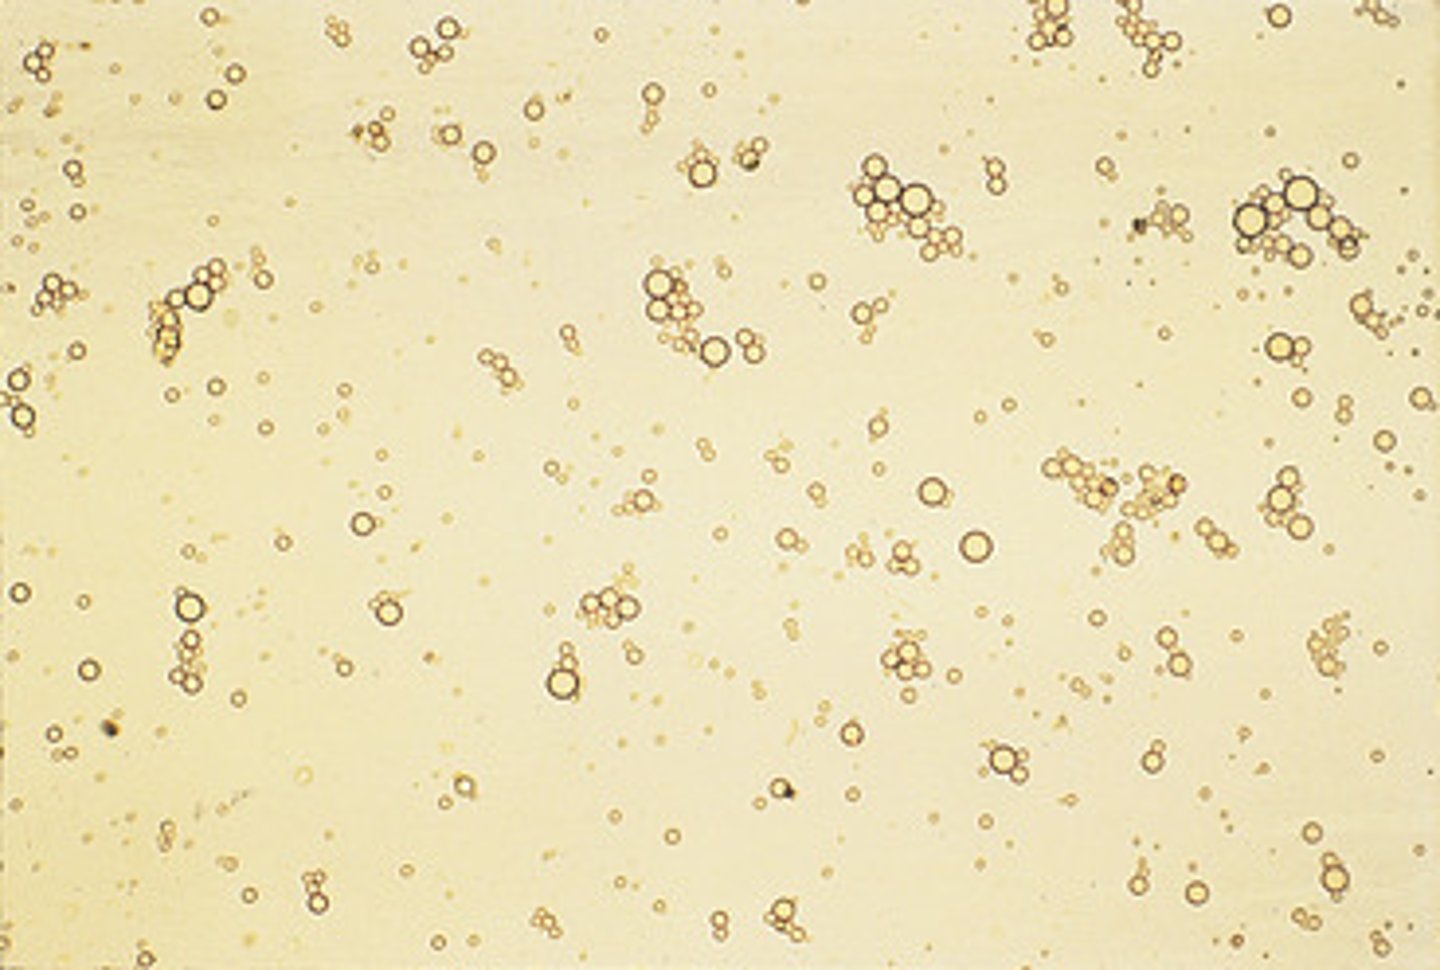

fat

urine

can be clumped

refractile